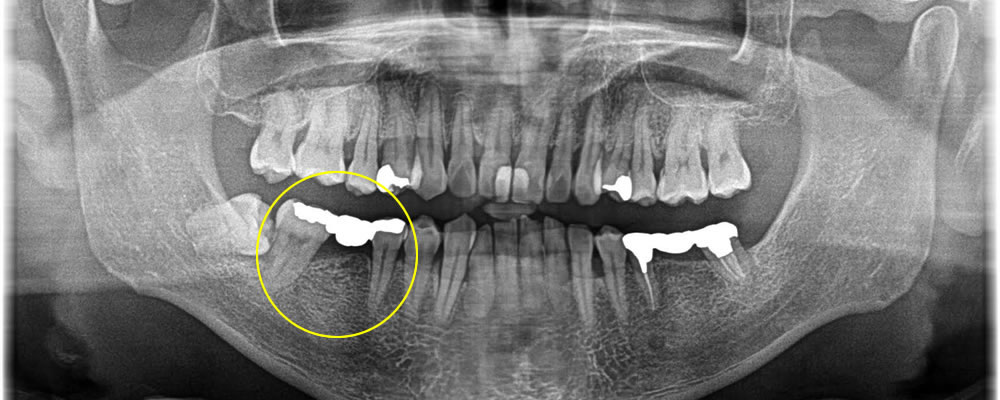

痛みのある奥歯をインプラントで治療した症例

年齢

50代

性別

女性

症例を見る